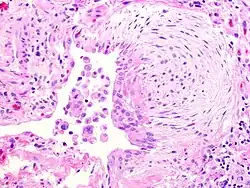

O fibroblasto é a célula constituinte do tecido conjuntivo e sua função é formar a substância fundamental amorfa. Tem um citoplasma ramificado e rodeado de um núcleo elíptico contendo 1-2 nucléolos. Os fibroblastos ativos podem ser reconhecidos pela abundante ocorrência de retículo endoplasmático. Amadurece, transformando-se em um fibrócito. É responsável pela biossíntese de colágeno do tipo 1. Produz substância intercelular e origina células de outros tecidos conjuntivos, são responsáveis pela regeneração.

Os fibroblastos sintetizam as proteínas colágeno e elastina, além das glicosaminoglicanas e glicoproteínas multiadesivas que farão parte da matriz extracelular. Essas células estão também envolvidas na produção de fatores de crescimento, que controlam o crescimento e a diferenciação celular. Os fibroblastos são as células mais comuns do tecido conjuntivo e são capazes de modular sua capacidade metabólica, a qual vai refletir em sua morfologia. As células com intensa atividade de síntese são denominadas de fibroblastos, enquanto as células metabolicamente quiescentes são conhecidas como fibrócitos.